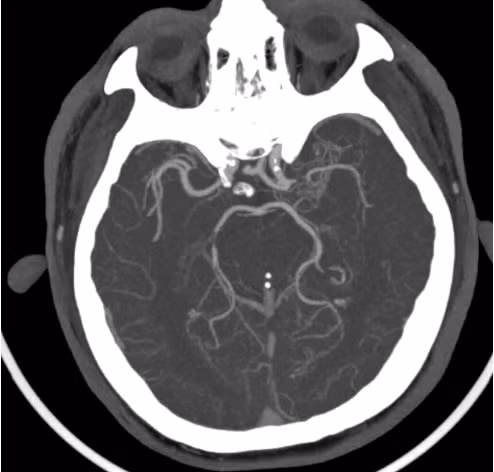

Ngay sau khi bơm thuốc tiêu sợi huyết ghi nhận sức cơ của bệnh nhân Đ. và N. đã cải thiện rõ rệt. Từ kết quả chụp CT mạch máu được thực hiện ngay sau bơm thuốc tiêu sợi huyết (Hình 2 và Hình 4) thấy cục huyết khối đã tiêu, tuy nhiên vẫn có sự hẹp của một động mạch lớn nội sọ ở cả 2 trường hợp.

| Hình ảnh hẹp động mạch thân nền của bệnh nhân P.T.N |